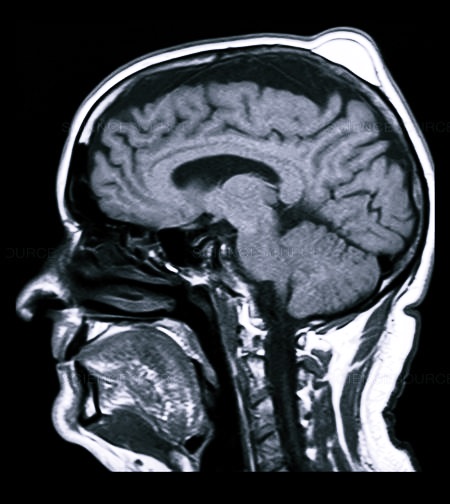

Первичный диагноз выставляется на основании внешнего осмотра, жалоб больного, данных анамнеза. Для его подтверждения иногда требуется проведение ряда инструментальных исследований:

- рентгенографии;

- МРТ или КТ;

- ангиографии;

- ультразвукового исследования.

На голове проводится и УЗИ исследование, помогающее определить видоизменения в тканях и костных структурах, иногда МРТ, в виде дополнительной меры диагностики.